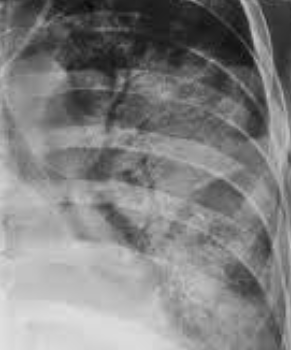

Patrón de consolidación IMAGEN

NO veo un carajo en la opacidad